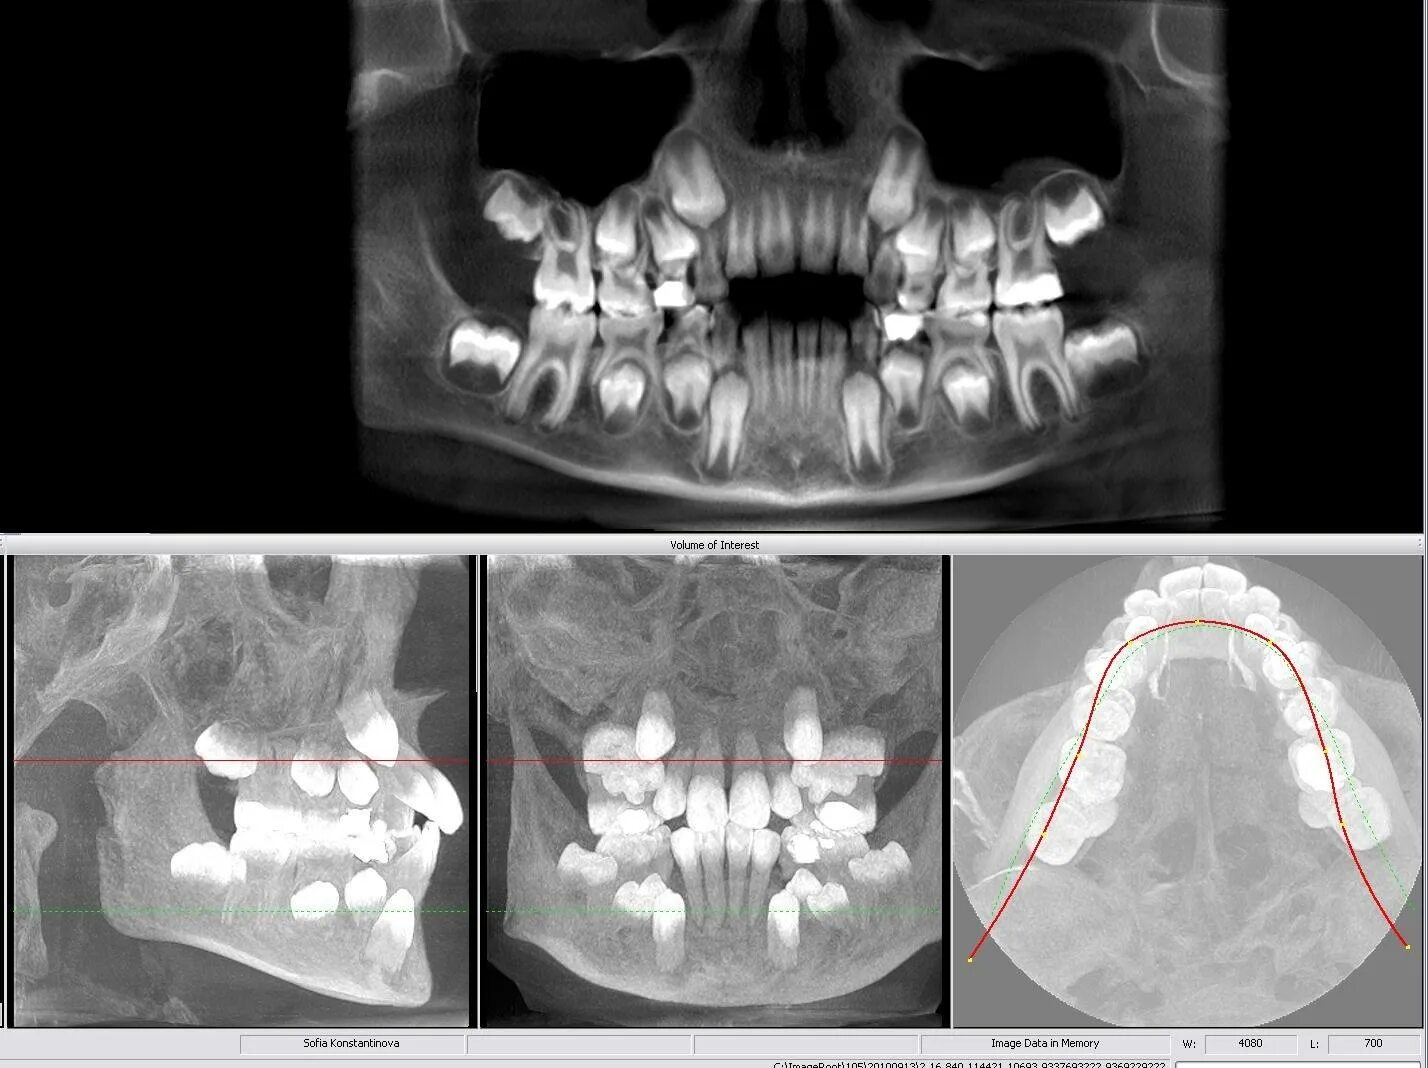

Опасно делать кт